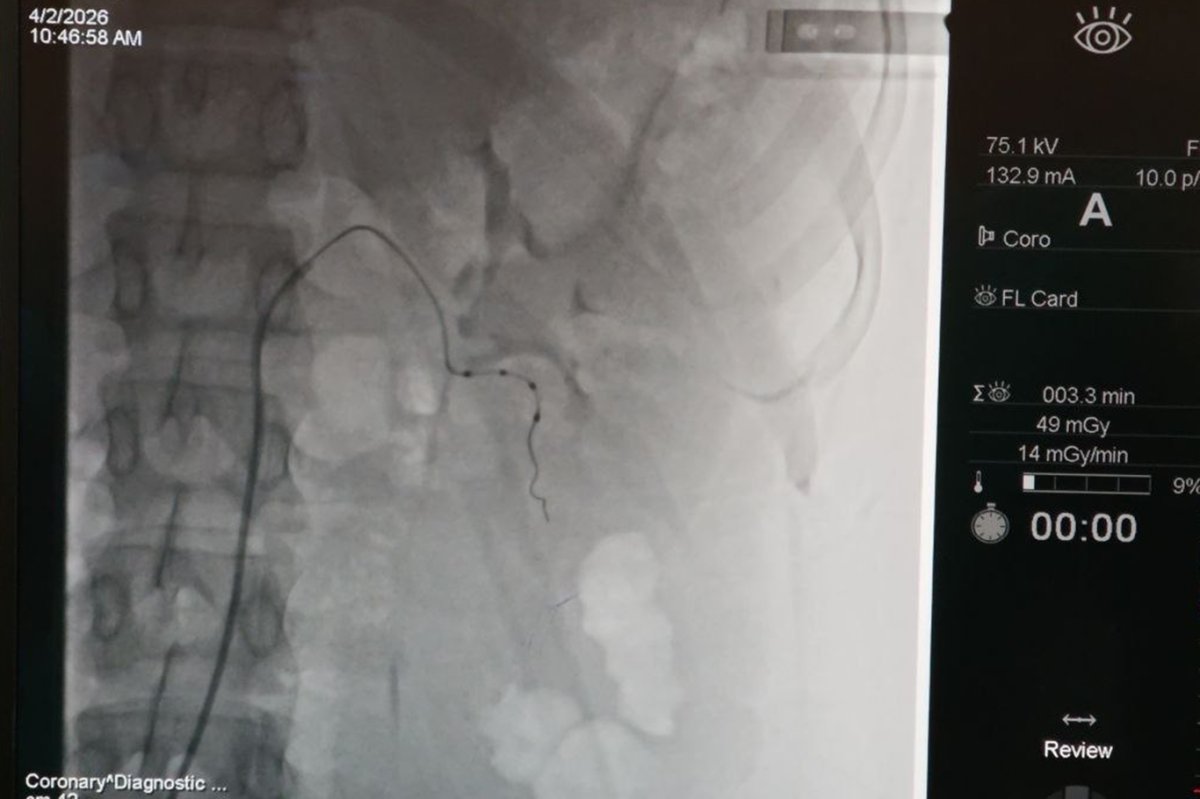

İnönü Üniversitesi Turgut Özal Tıp Merkezi Kardiyoloji Anabilim Dalı Öğretim Üyesi Prof. Dr. Hasan Pekdemir ve ekibi tarafından gerçekleştirilen başarılı renal arter denervasyonu işlemiyle hasta sağlığına kavuştu.

Bölgede bir ilk ve Malatya'da ilk kez gerçekleştirilen işlem hakkında İLKHA muhabirine konuşan Prof. Dr. Hasan Pekdemir, uygulamanın gebelik planı bulunan ancak tedavisinin bunu sınırlandırdığı genç bir hastaya başarıyla yapıldığını ve tansiyon değerlerinin kontrol altına alındığını ifade etti.

Bu noktada devreye giren renal arter denervasyonu yönteminin, böbrek damarlarının etrafındaki sempatik sinirlerin ablasyon yöntemiyle etkisiz hale getirilmesine dayandığını belirten Pekdemir, yöntemin etkisini şu sözlerle anlattı:

"Bu sinirleri yaktığımızda tansiyonu yükselten sinyallerin beyne iletilmesi engelleniyor. Böbreğe giden yanlış uyarılar ortadan kalkıyor. Bunun sonucunda damarlar genişliyor, tuz ve su tutulumu azalıyor ve hastanın tansiyonunda ciddi düşüşler sağlanıyor."